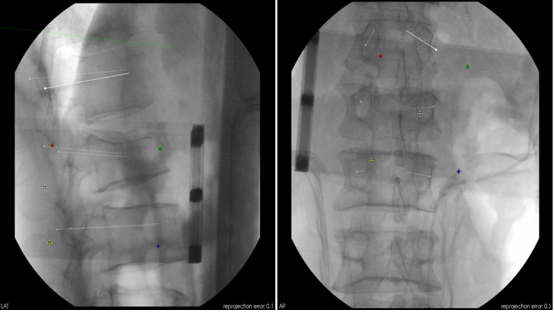

在刘时璋主任精心筹备、悉心安排下,术前手术医生团队和手术机器人技术保障团队密切协作,详细分析了患者腰椎CT资料,精确规划了椎弓根螺钉通道位置及各项参数,重建模拟椎弓根螺钉植入后三维图像,并不断优化方案使其更精准、安全,并进行了手术机器人使用的术前演练。手术当天,常彦海主任医师和陈明副主任医师共同为患者实施了手术。术中,借助C臂获取患者腰椎正侧位影像及标记定位,将其传入机器人系统与患者术前腰椎CT质料匹配映射,确定了每个螺钉的实际穿刺通道,通过机械臂在压力监测和光学追踪引导下依次钻入导针,最后精准植入6枚椎弓根螺钉。脊柱周围毗邻重要神经和血管,椎弓根螺钉通道空间有限,常规经皮植钉技术风险大,容易发生神经损伤等并发症,且术中需要反复透视,手术机器人很好弥补了这些弊端,相当医生有了“透视眼”和“第三只手”,使手术操作更加智能化、精准化。